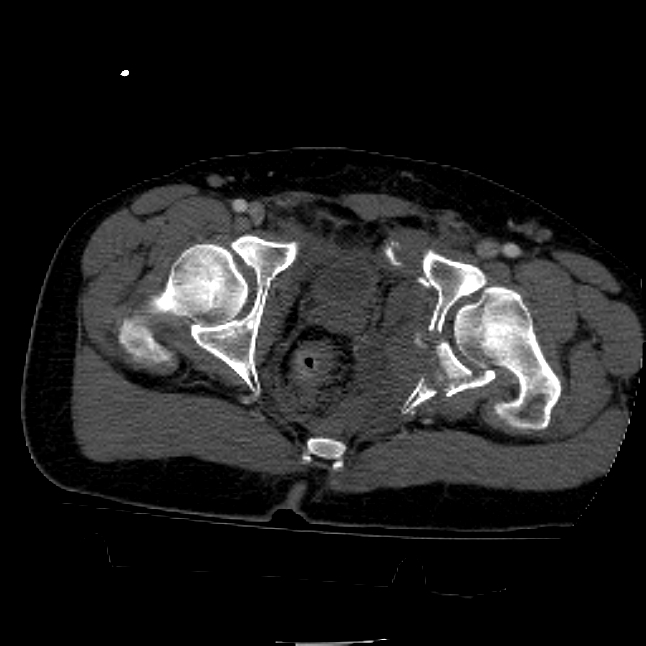

25 yo brittle diabetic, became hypoglycemic and passed out on his motorcycle. Sustained bilateral lateral Hoffa fractures with associated LCL injury on the right and right distal radius fracture. I have questions regarding his pelvic ring/acetabular fracture on the left. Appears to be a very low posterior column fracture with associated posterior wall, marginal impaction. Superior and inferior rami fractures as well on the left giving him a floating segment of inf ramus/ischium/posterior column, but no detectable posterior ring injury. Should the posterior column/posterior wall fracture be addressed surgically because of the marginal impaction? Or is this fracture low enough to be treated non-operatively? I appreciate the input.

It's an interesting case. The plain films show the impaction, but most of the joint looks pretty good. The CT cuts look awful, though.

The impaction is so big I don't think I would ignore it. It IS down low, but it takes up almost the whole southern hemisphere of his joint.